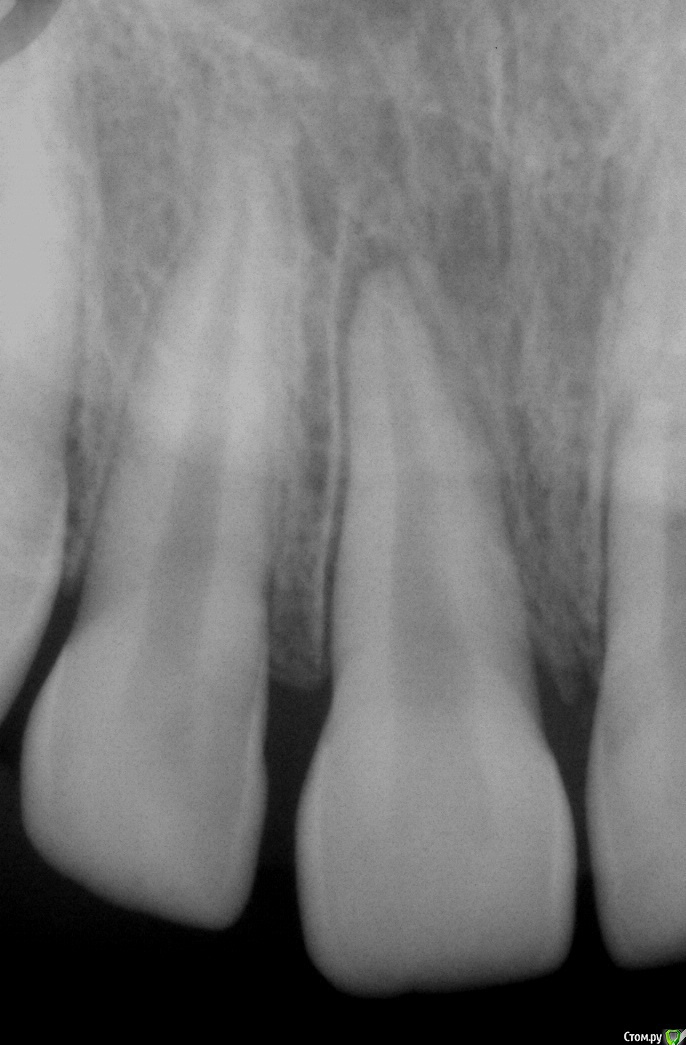

simpsons Опубликовано 13 декабря, 2016 Поделиться Опубликовано 13 декабря, 2016 Пациент пришел после ЧЛО. Катался на велосипеде. 11 лет. Боль при прикосновении к забам,подвижность 11,21 зубов 3 степени. Подскажите ,как правильно поступить в данной ситуации? Ссылка на комментарий

Тань Опубликовано 11 июня, 2018 Поделиться Опубликовано 11 июня, 2018 Сегодня пришёл парень 9,5лет с жалобами на подвижность коронки 11 зуба и боль при касании. В анамнезе в!!! апреле!!! упал с турника, была боль и небольшая подвижность. В клинике по месту жительства делали снимок, сказали динамически наблюдать, ничего не делали. Через некоторое время подвижность усилилась, пошли к знакомому ортопеду,он сказал что ничего кроме удаления, что ничего кроме съемного протезирования и в дальнейшем имплантации не сделать Пришёл к нам. Ортодонта нет, ортопеда нет, все выходные... Мне предстоит принять решение. Склоняюсь к удалению, но не решаюсь, знаю, что есть такая методика:оставить корень, чтобы не "ушла" кость. Хирург тоже не решился сразу удалять корень, пока удалил коронку, я провела эндо и временно каласепт под септопак оставила, вдруг можно сохранить хотя бы кость с корнем до имплантации. Жду ортодонта и ортопеда с выходных, а что вы, коллеги, на это скажете? Ссылка на комментарий

crown Опубликовано 12 июня, 2018 Поделиться Опубликовано 12 июня, 2018 Пока с гидроксидом кальция хочу повести, будет ли апексификация?Судя по снимку там все сформировано, разве нет? Ссылка на комментарий

red_butler Опубликовано 12 июня, 2018 Поделиться Опубликовано 12 июня, 2018 На снимке удаленной коронковой части, похоже резорбция... Ссылка на комментарий

vse32 Опубликовано 12 июня, 2018 Поделиться Опубликовано 12 июня, 2018 На снимке удаленной коронковой части, похоже резорбция... Если только наружняя, типа цервикальной. На нее действительно немного похоже. А так может и цервикальный, круговой кариес. Ссылка на комментарий